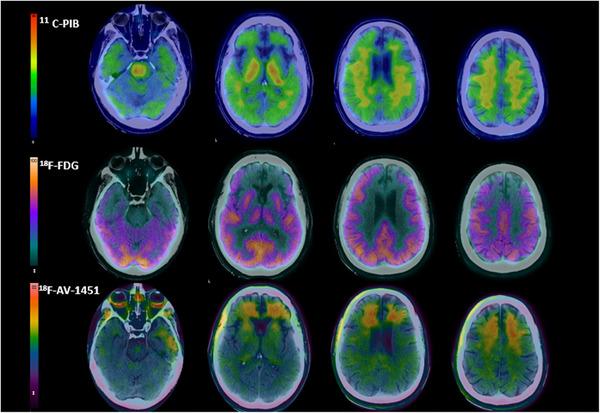

Behavioral variant frontotemporal dementia (bvFTD): PET biomarker characterization of metabolism (18F-FDG), amyloid (11C-PIB) and tau (18F-AV1451) and its clinical correlate - analysis of a cohort from Argentina.

We studied a cohort of bvFTD patients (n = 20) and controls (n = 21) with three different PET radiotracers (18F-FDG, 11C-PiB, and 18F-AV1451).

In bvFTD patients, 18F-FDG PET showed significant hypometabolism in frontotemporal regions, along with hypermetabolism in the precentral gyrus, compared to normal controls. 11C-PIB did not reveal a pattern typical of Alzheimer's disease, yet increased uptake was notably observed in the precentral region. We found 18F-AV1451 uptake in frontal lobe, parietal, precuneus, cuneus, posterior cingulum, highly significant in bvFTD with respect to NCs.

First bvFTD study using 18F-FDG, 11C-PIB, and 18F-AV1451 PET in a Latin American cohort. Frontotemporal hypometabolism with compensatory precentral hypermetabolism due to amyloid. Amyloid deposits observed in the precentral gyrus without an Alzheimer's-like pattern. 18F-AV1451 shows limitations in specificity for bvFTD pathology. Study provides new insights into PET biomarker utility for bvFTD clinical assessment.